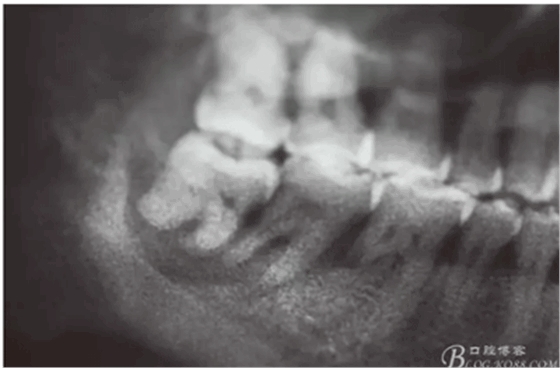

患者,白xx,女,40歲。主訴:右側(cè)下后牙牙探針齦反復(fù)腫痛,不能吃東西數(shù)月。??茩z查:48松動(dòng)Ⅲ,47松動(dòng)Ⅱ,牙周探針:48牙周袋均8mm,47遠(yuǎn)中牙周袋8mm,x全景片檢查:48牙槽骨弧形吸收至根尖區(qū),陰影較大。47遠(yuǎn)中牙槽骨吸收至遠(yuǎn)中根尖部,近中牙槽骨部分角形吸收。診斷:拔除48,試保留47.同期實(shí)行47牙周刮治術(shù)。患者同意治療方案,簽知情同意書。

圖2.局部的放大影像情況。48骨質(zhì)吸收至下頜管邊緣,陰影范圍廣,拔除48后牙槽窩處理要小心。